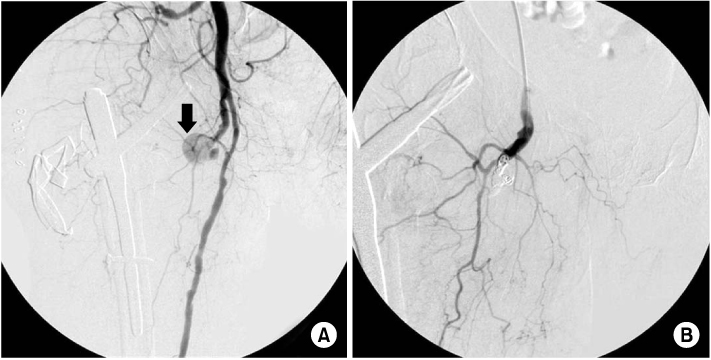

Fig. 2

Clinical photograph of thigh swelling with knee flexion contracture. Notice the swelling of injured limb is more than twice the circumference of the contralateral limb.

Fig. 2 Clinical photograph of thigh swelling with knee flexion contracture. Notice the swelling of injured limb is more than twice the circumference of the contralateral limb.